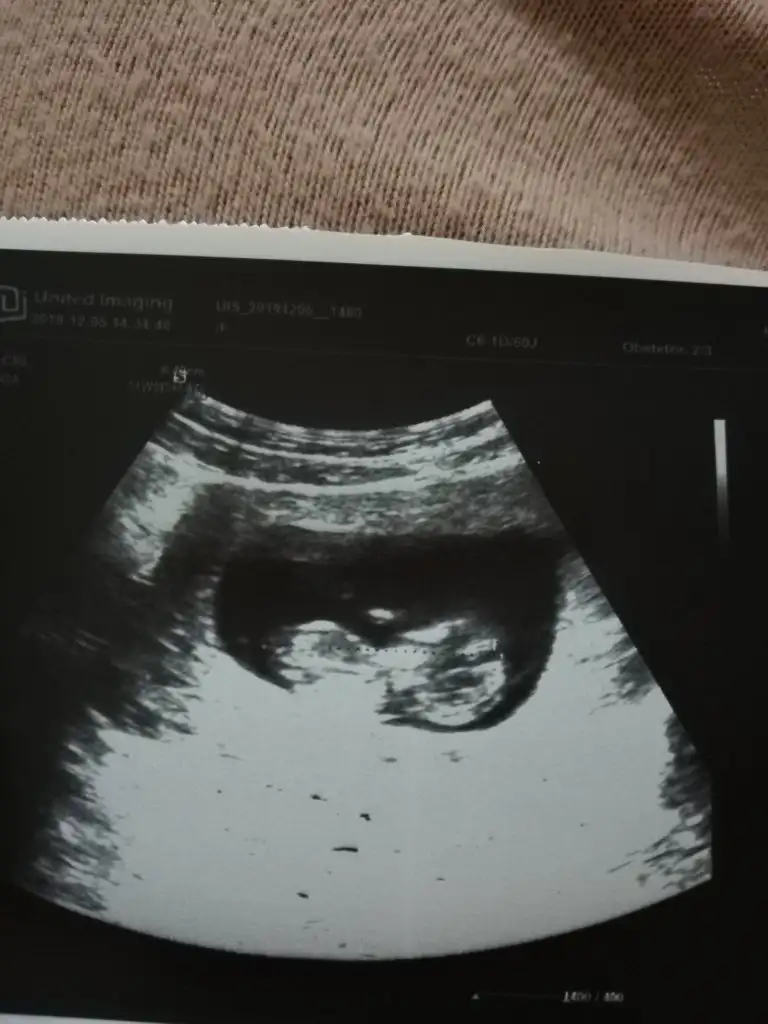

Buda bizim minnak çok teşekkür ederim canımTabiki

Kaç haftalık buna göre kız ama nub için 11 yada 12 hafta usg de paylaşın tahmin ederizBuda bizim minnak çok teşekkür ederim canım![]()

Canım 11+6 burda tahminin var mıKaç haftalık buna göre kız ama nub için 11 yada 12 hafta usg de paylaşın tahmin ederiz

Net degil usg ama sanki sanki kız gibi gibi diye ekliyorumCanım 11+6 burda tahminin var mı